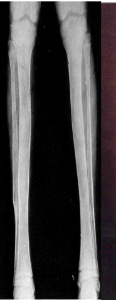

Osteoid Osteoma X-ray

Target-like radiolucent lesion (actual tumor or nidus which may be centrally mineralized) which is sharply demarcated with surrounding rim of thick/dense reactive cortical bone